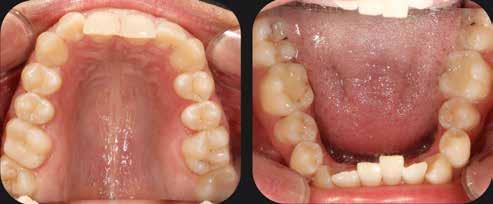

A 28 éves hölgypáciens is elsősorban a szép mosoly elérésének igénye miatt szeretett volna fogszabályozást, bár tudomása volt a mélyharapásáról (1–5. képek).

A kezelési célokat a fogívek tágítása a megfelelő mosolyszélességhez és az alsó frontfogak torlódásának feloldásához, valamint a mélyharapás és a kismértékű disztálharapás korrekciója jelentették (6–11. képek).

Passzív önligírozó fix fogszabá-

lyozó készülékkel 15 hónapig tartott a kezelése. Az ilyen mélyharapásos esetekben nagyon fontos, hogy a harapásemelésnél nem történik intrúzió a felső fogíven, mert az kifejezetten negatívan befolyásolná a vertikális mosoly-display-t! A fogszabályozó kezelés után, ahogy az általában lenni szokott, a bölcsességfogak eltávolításra kerültek. Mint minden esetben, a fogszabályozás aktív fázisa után a retenció, a passzív helyben tartó fázis a kezelési eredmény megtartásához rendkívül fontos!